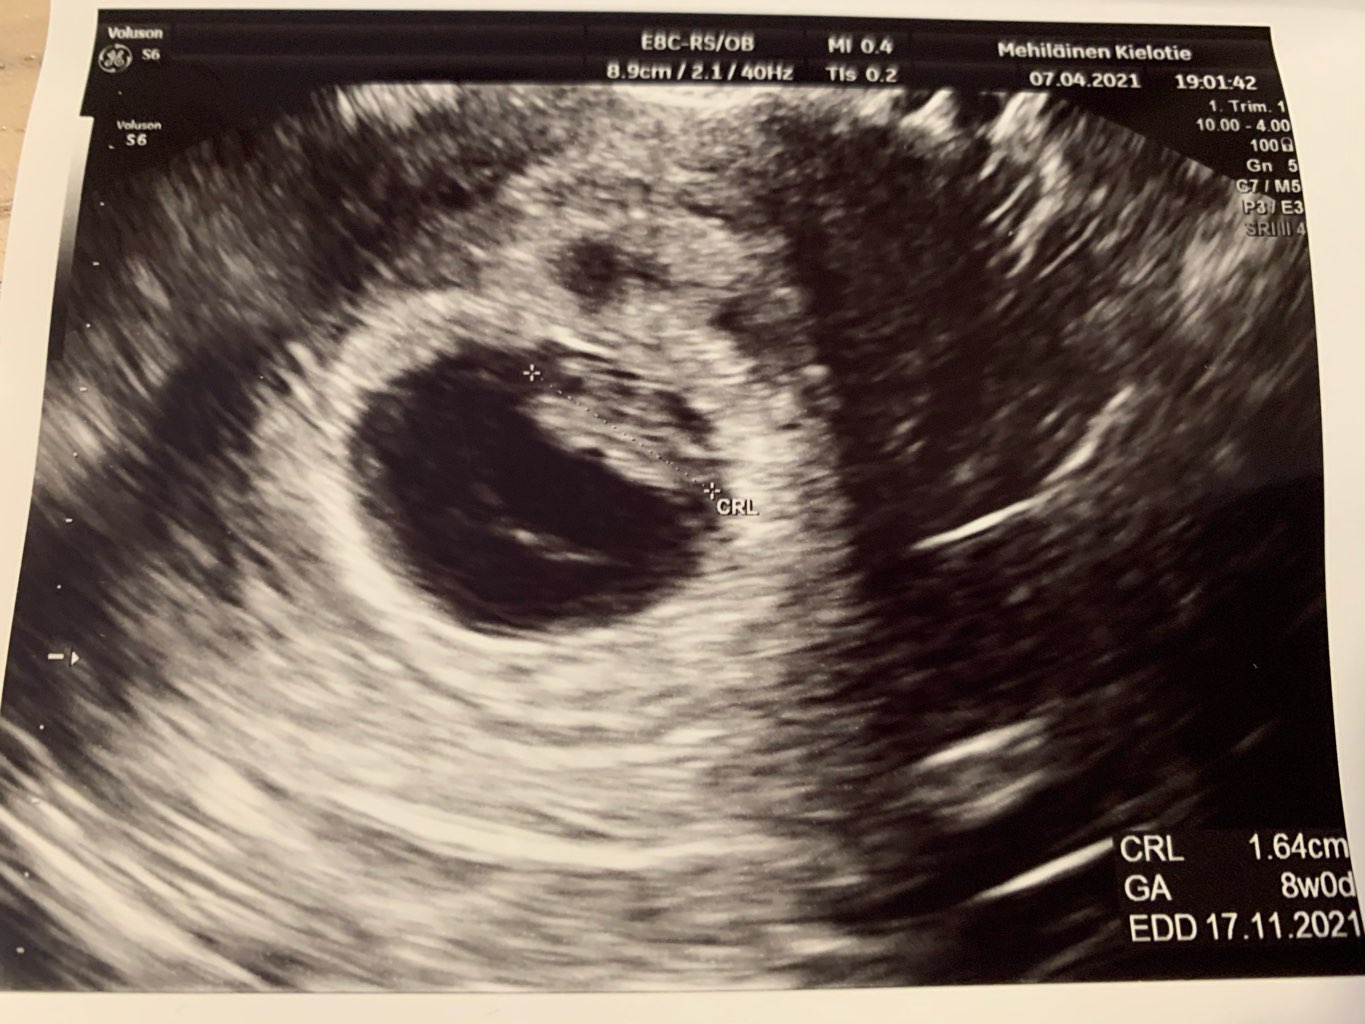

A teraz sie chwale.

Niesamowite bylo zobaczyc jak macha konczynami

Załączniki

• IMG_2469.jpg

IMG_2469.jpg

187 KB · Wyświetleń: 129